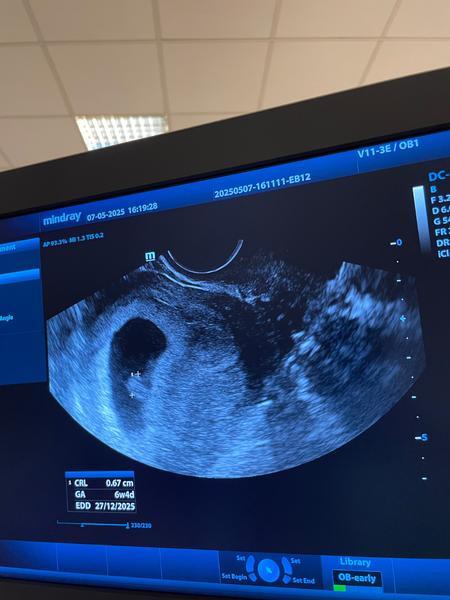

Viditeľnosť bábätka na ultrazvuku v 5. až 6. týždni

V 5-6 tt staci, ak potvrdi tehotenstvo v maternici a vyluci mimomaternicove. Mal by tam byt gestacny vak, mohol by byt vidiet aj zltkovy vak, dokonca mozno aj embryonalnu strukturu. Srdiecko moze byt ale vobec este nemusi . zalezi od ovulacie, ak bola trochu neskor uplne staci potvrdit gestacny vak v maternici.

To znamena ze 5 tyzden ukonceny plus 2 dni, teda prebieha 6 tyzden. Aj appka aj sestricka maju pravdu. Vzdy sa to rata od poslednej menstruacie, lebo ovulaciu doktor nevie, spermie dokazu prezit aj 7 dni. Potom ked sa bude dat babo zmerat ti dr povie presnejsie urci to podla jeho velkosti.

Ahojte baby,som tehotná podľa poslednej menštruacii 6+4 tyždne